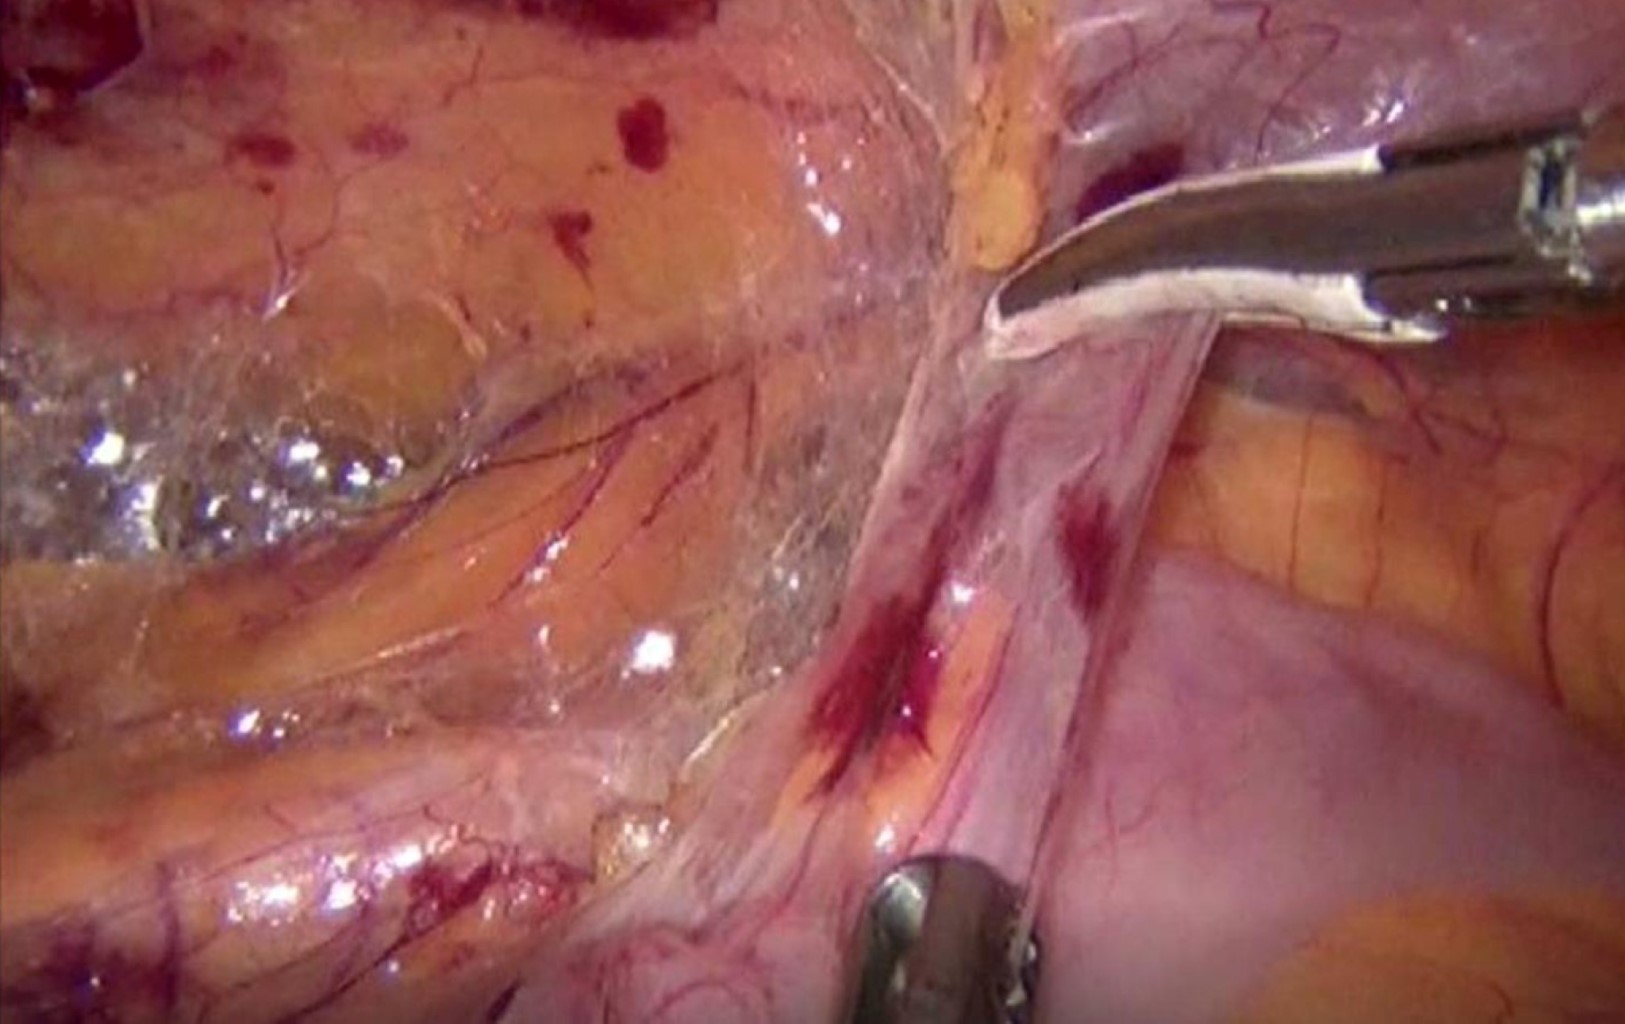

Figure 1

Figure 2

Figure 3

Figure 4

Figure 5